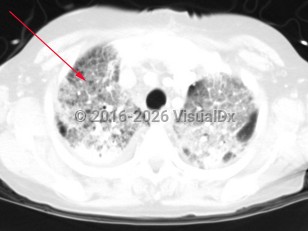

Symptoms include fever, cough, and shortness of breath. Symptoms may differ depending on the type of pneumonia (either segmental or bronchopneumonia). Patients with a segmental pneumonia can present with abrupt onset of fever and pleuritic chest pain. These patients tend to develop bacteremia more frequently than those with bronchopneumonia. Patients with bronchopneumonia can present with constitutional symptoms, tachypnea, and mild fever. Haemophilus influenzae more commonly presents as a bronchopneumonia.